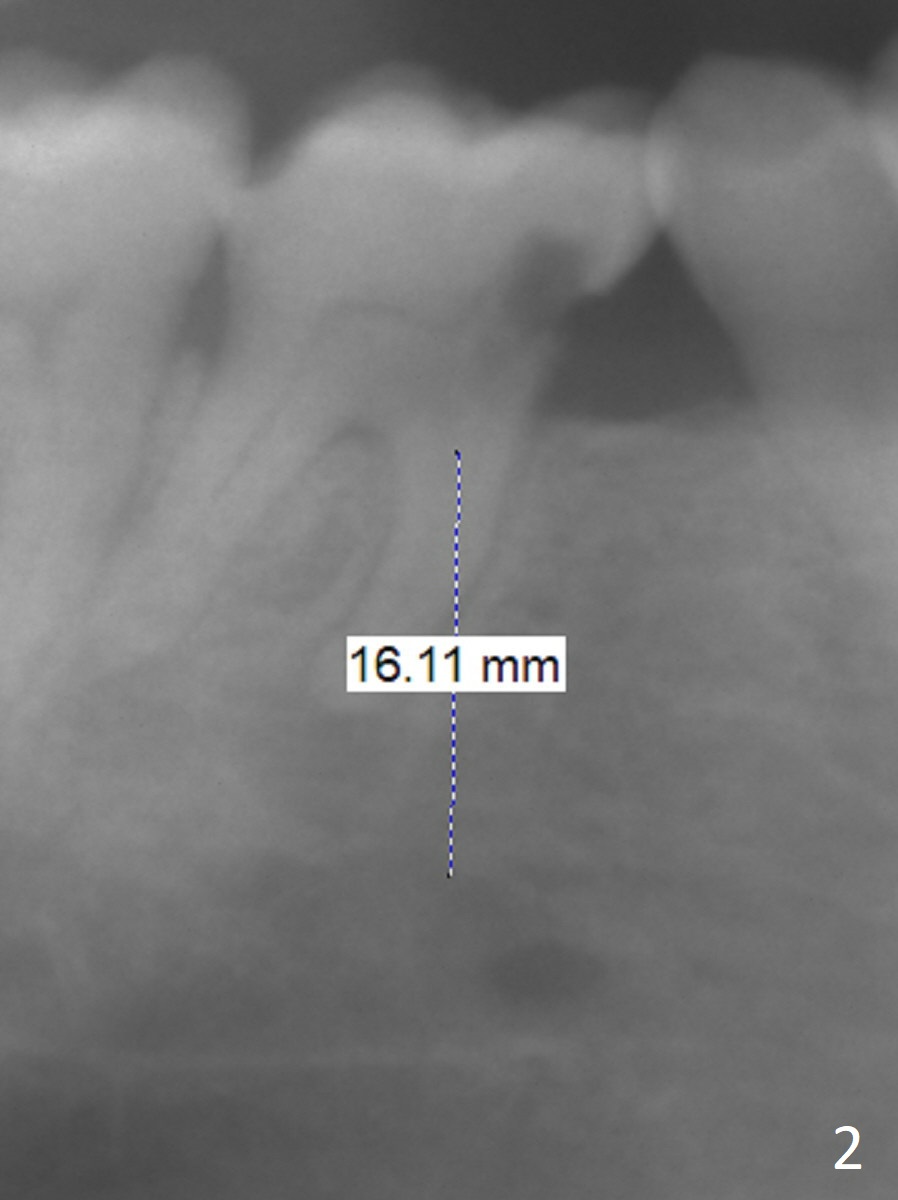

A 58-year-old man has history of temporomandibular joint disorder as related to severe occlusal breakdown and missing tooth #18 (Fig.1,4). The tooth #29 is also missing; the tooth #30 has shifted and tilted mesial. Severe pain develops at #30 two years after MOL composite (Fig.3). The patient insists on extraction and implant, although pulpotomy has been done to alleviate the pain. Although there is sufficient bone height, IS implants will be used because of primary stability and apparent better implant/abutment binding as compared to IBS (with tendency of screw loosening). Osteotomy will be initiated in the mesial socket at #30. Measure the whole length of drills. Find 17-8 mm mark, which will be used as soft tissue landmark.